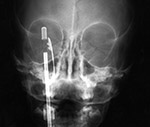

| Retained drill guide |

CT scout image of a patient assaulted with a screwdriver. He suffered no long term sequelae. |

| Frontal and lateral views of the right wrist after placement of a volar T-plate and screws for a comminuted distal radius fracture. On the lateral view there is a retained drill guide (arrow) that was inadvertently left in place. It should have been removed at the end of the surgical procedure. It is not evident on the AP view and was initially overlooked by both an MSK radiologist and the patient's orthopedic surgeon. |